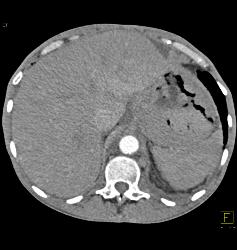

Gastric Lymphoma With Nodes and Ulceration